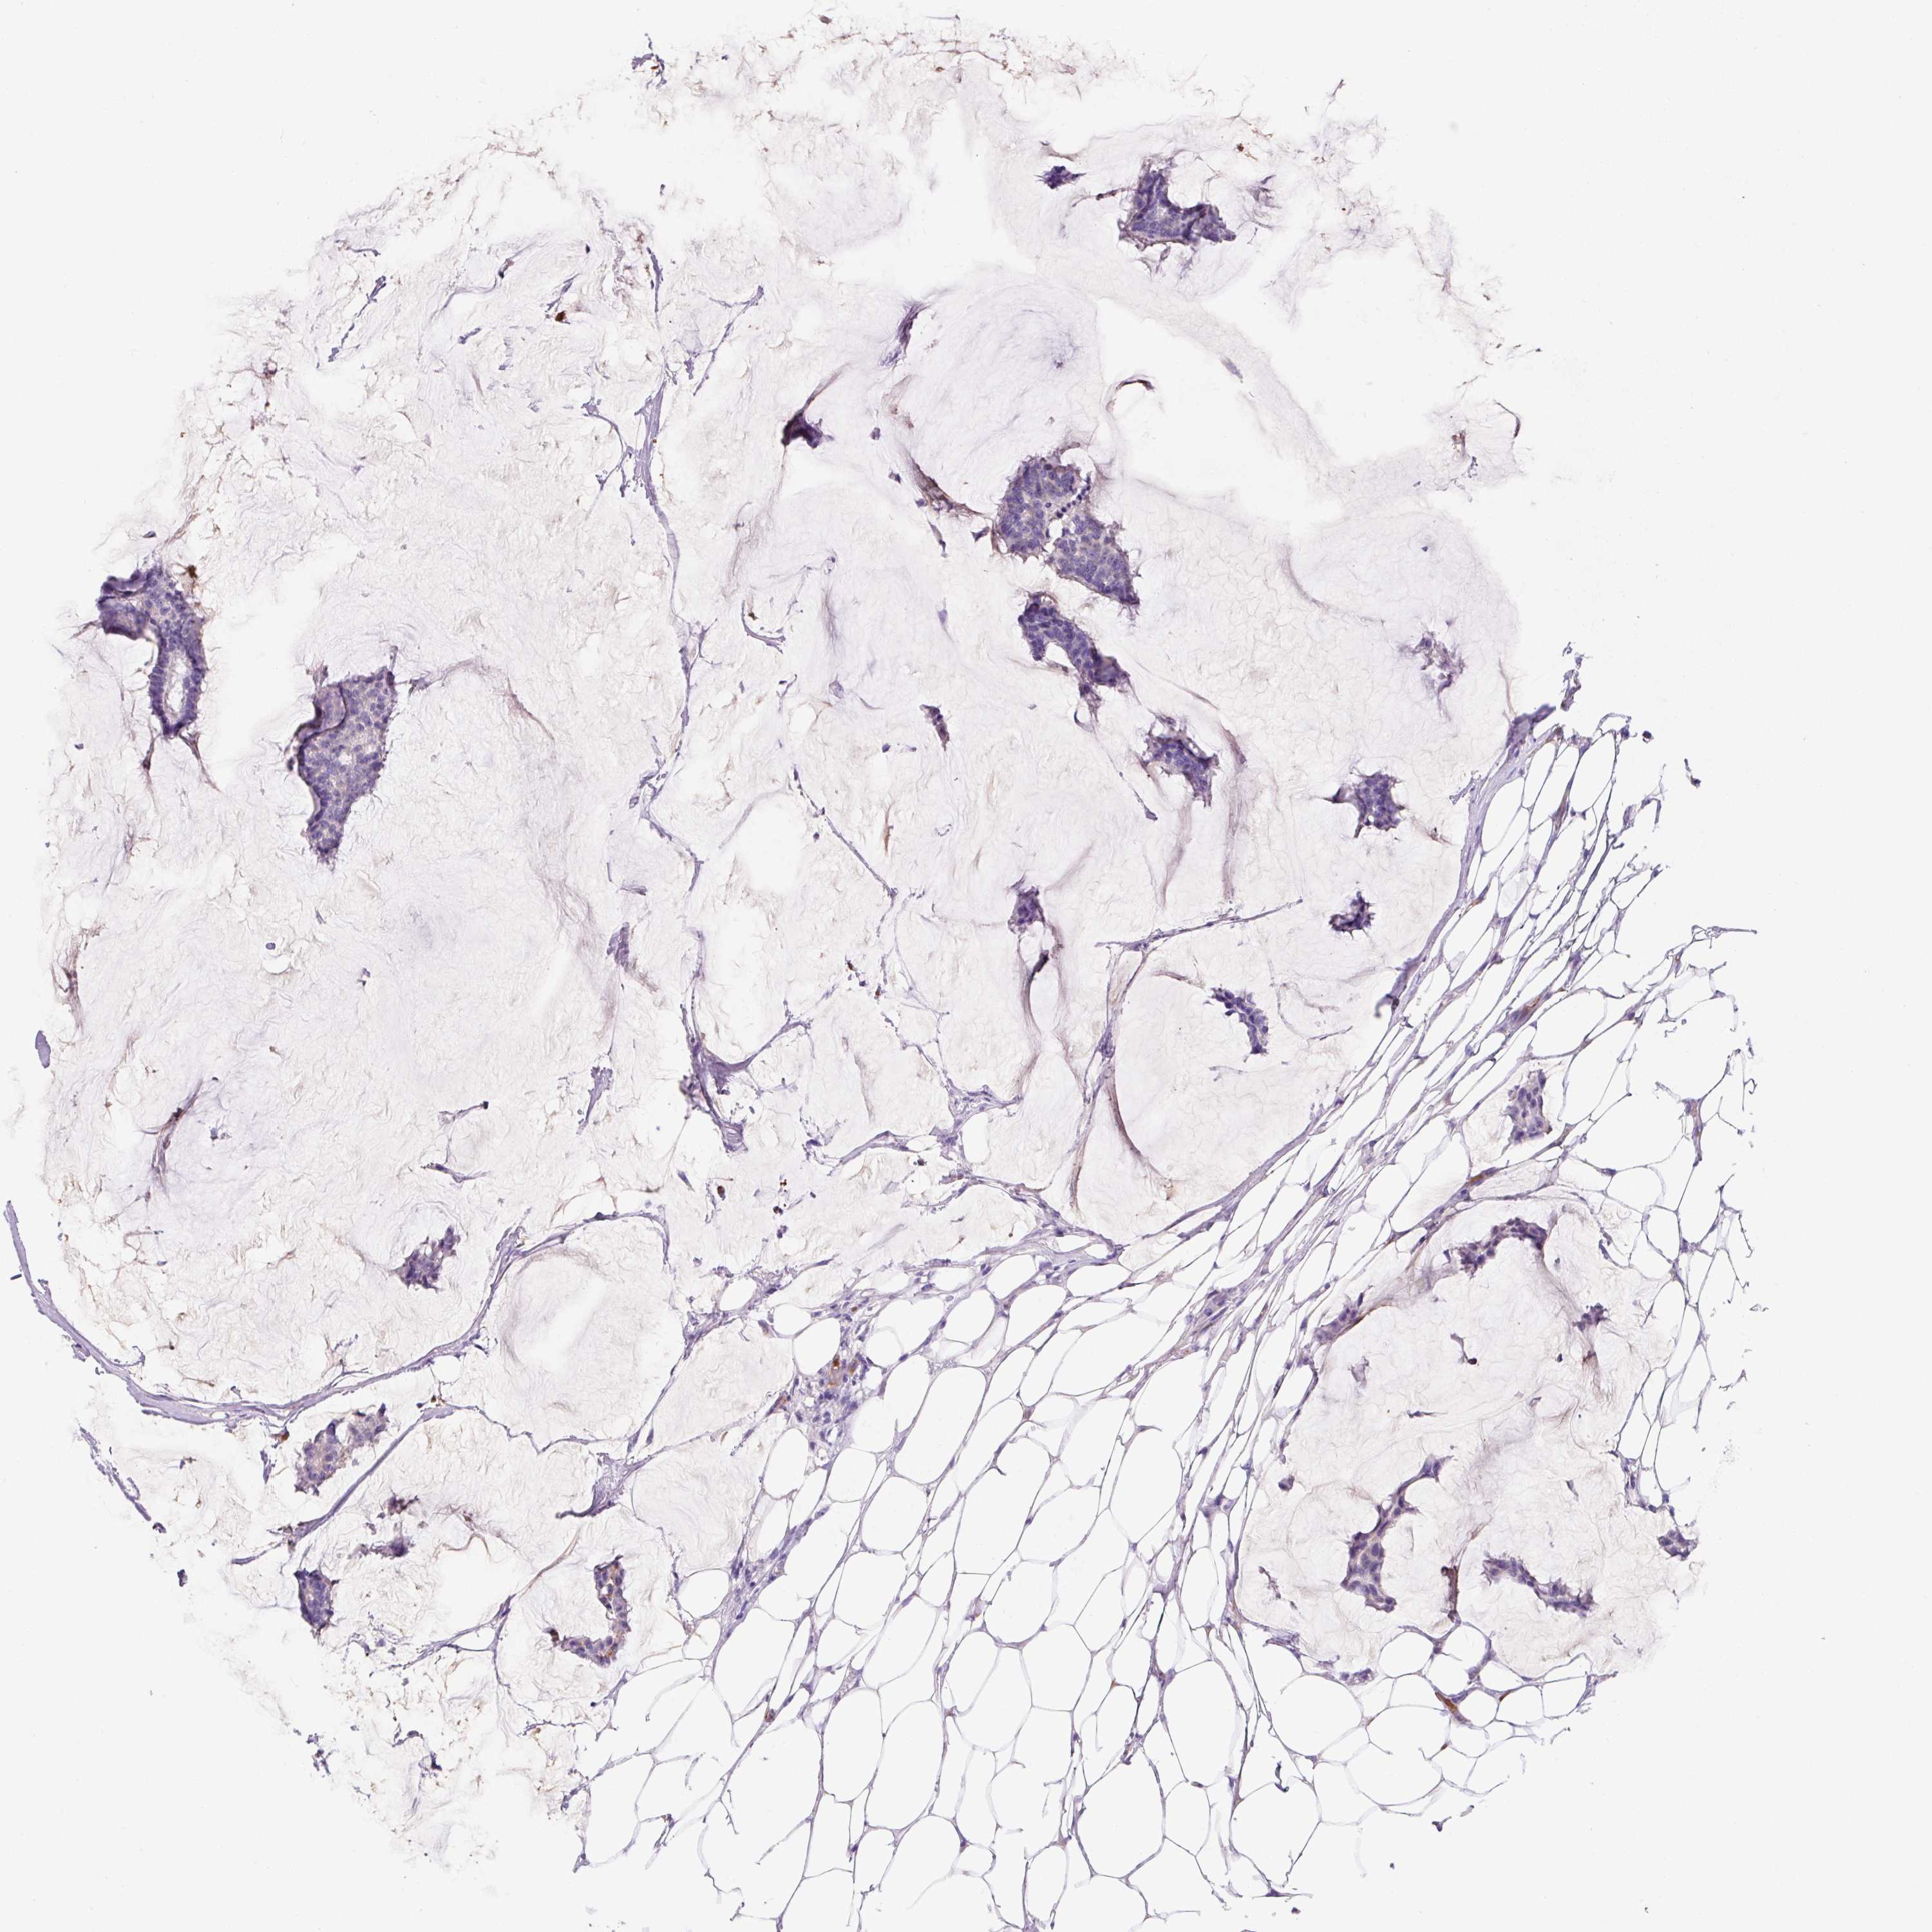

BRCA TCGA BRCA VALIDATION PROTEIN EXPRESSION

ANTIBODIES

AND

VALIDATION